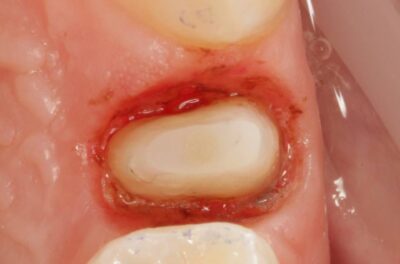

Специализация: терапия(эндодонтия), ортопедия, имплантология.